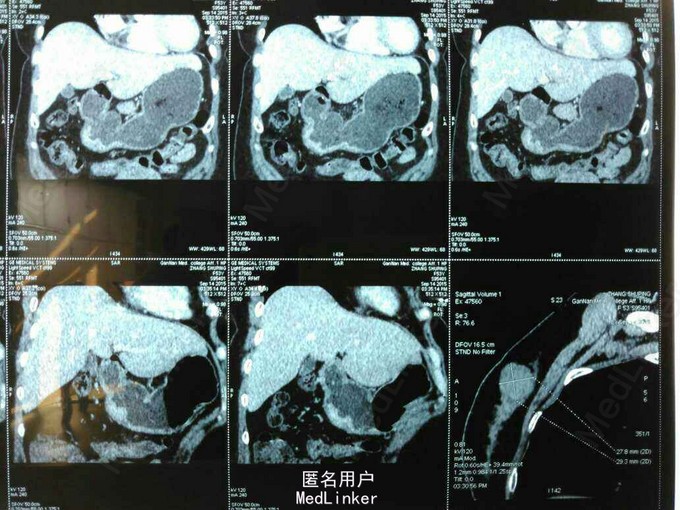

患者,女性,53岁,因“反复上腹部痛1年余,加重1周”入院。患者一周前在我院门诊胃镜并活检提示胃窦低分化腺癌。

查体无特殊。辅查:腹部增强CT提示:胃窦壁不规则增厚,考虑胃癌。腹部彩超:肝胆胰脾未见异常。

诊断:原发性胃癌。治疗:胃癌根治术。